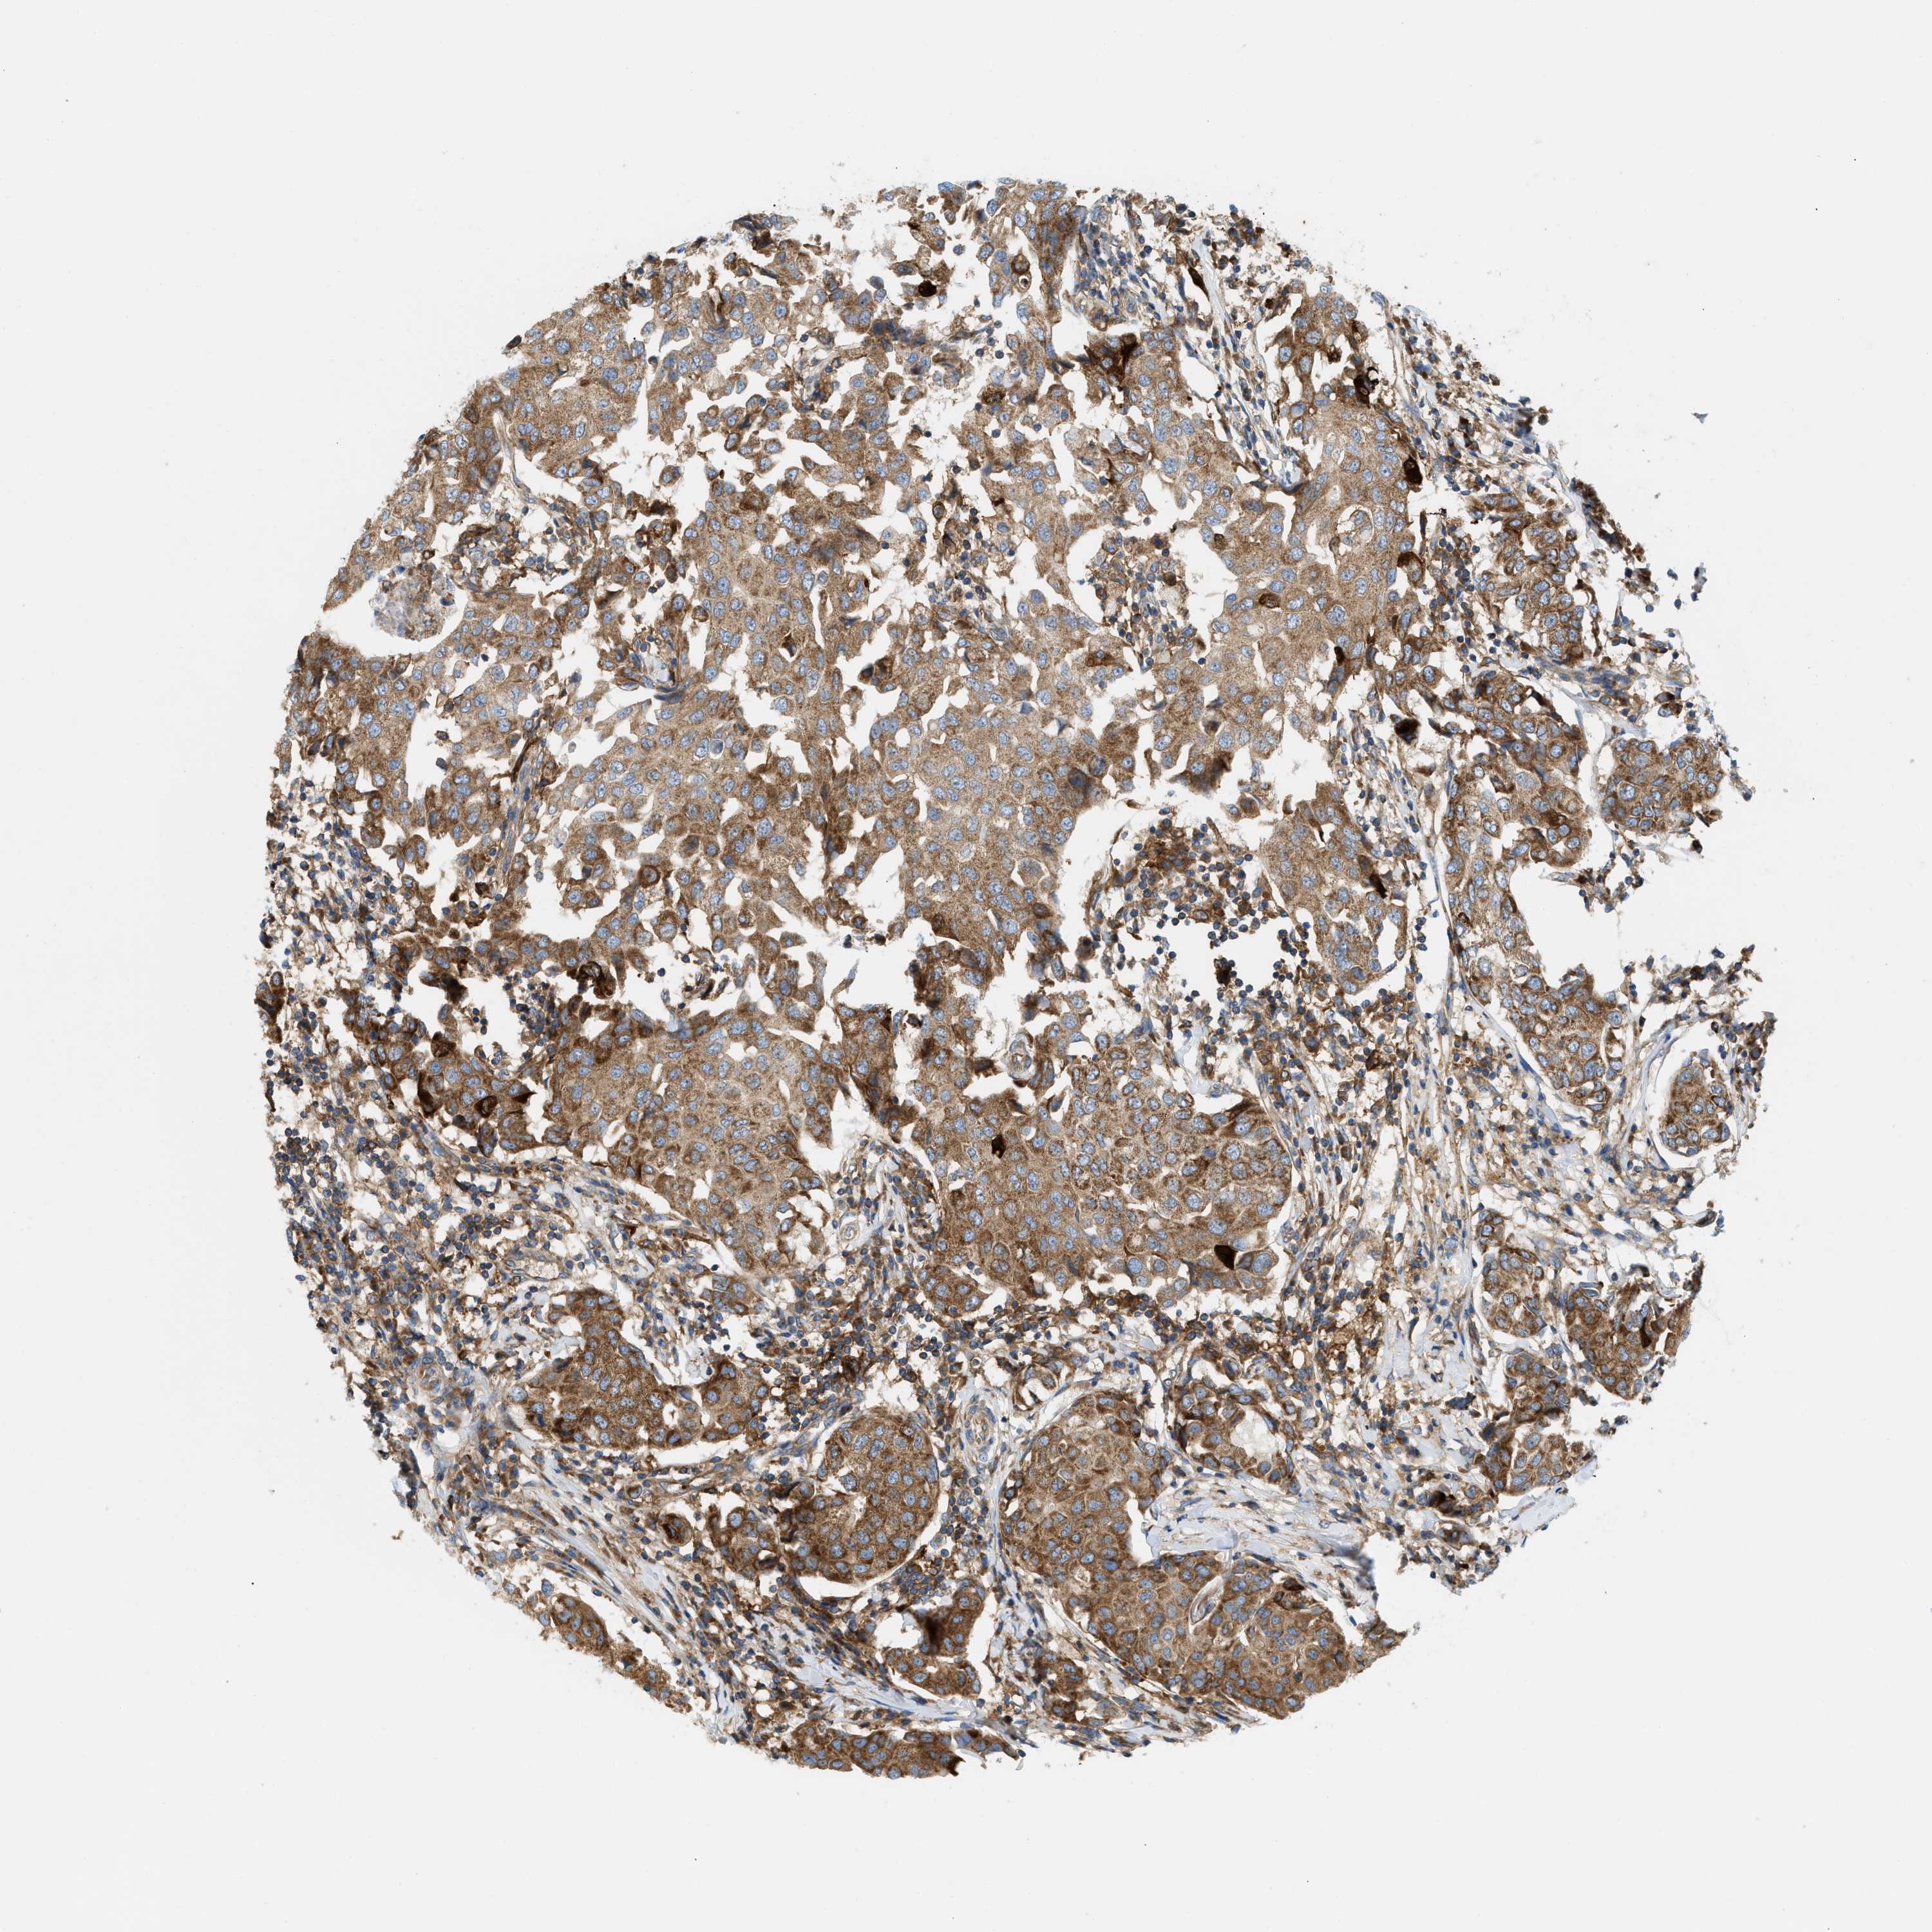

CANCER BREAST CANCER Show tissue menu

BRCA TCGA BRCA VALIDATION PROTEIN EXPRESSION